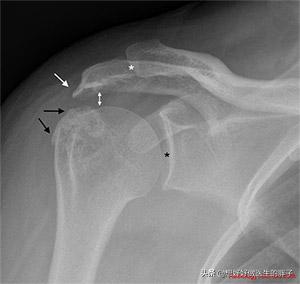

导致肩关节出现疼痛的问题非常多,比如常见的肩关节撞击综合症、肩袖损伤、钙化性冈上肌腱炎,或者是其他的一些问题,那么在进行治疗之前,我们首先要最基础的做一个肩关节的x线片子,明确关节内是否有骨髓形成,是否有明显的肩关节间隙的狭窄?是否有钙化?是否有明显的撞击?(下图就是一个典型的肩关节撞击综合症的x线片子,大家看到白色的箭头就是由于肩峰与肱骨大结节撞击形成的骨赘,黑色的箭头是在肱骨大结节上形成的骨质增生,这种情况很可能肩袖也发生了损伤)请大家记住这个图片,因为下面讲康复锻炼的时候也会用到这张照片。

谢医生把下面这张照片再次发上来,目的是为了告诉大家,在我们身边很多人会告诉您:肩关节出现了疼痛就甩肩吧,站在那儿画圈儿,这个动作在运动医学领域是极度不推荐的,因为做这个动作如果一旦患者存在了肩关节撞击综合症,而且在临床上很多肩痛都是由于肩关节撞击中国症导致的,在甩动的过程当中会加大肱骨大结节与肩峰的撞击,会导致肩袖由退变变为撕裂。